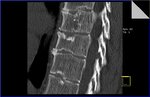

Ein Foto meiner "inneren Schönheit" hab ich mal angehängt.

Ein Foto meiner "inneren Schönheit" hab ich mal angehängt.